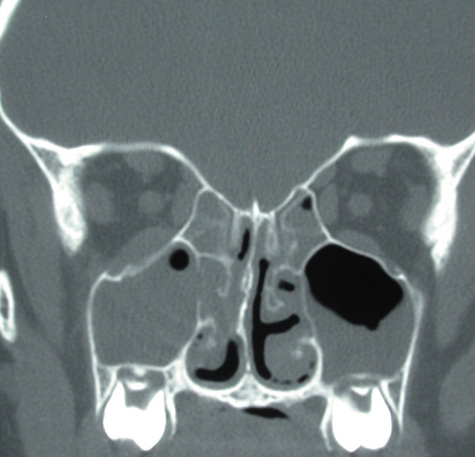

Computed tomographic findings in patients with both forms of the disease demonstrate areas that are almost metallic in density. These foci of irregularly calcified bone on CT may be pathognomonic (Fig. 22). On MRI, these areas appeared bright on T1-weighted imaging and have decreased signal on T2-weighted images, which may be related to the presence of ferromagnetic materials such as iron and manganese within the fungal concretions.115

Fig. 22. Aspergillosis. Computed tomography shows areas of extreme density of the ethmoidal bones.